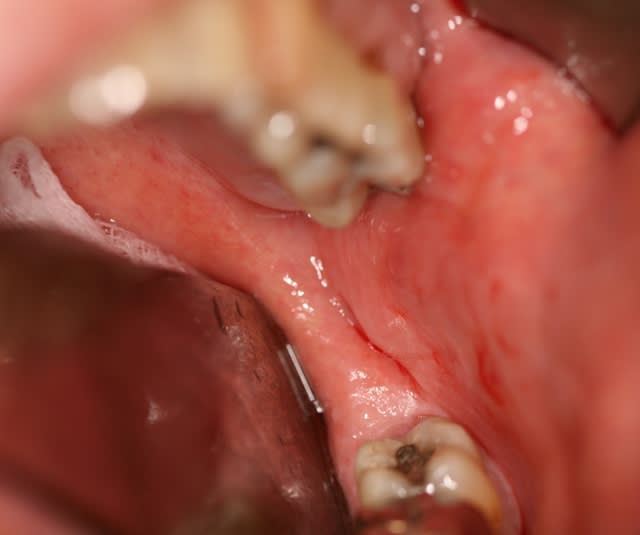

en prime je te montre le côté gauche.

Face à cette cavité kystique qui ne saigne pas, quelle attitude à adopter avant de refermer ?

Une cavité kystique donne toujours cette situation mais ne t'inquiète pas au bout de quelques minutes sans aspirer cela est totalement rempli de sang.

Pour autant j'ai mis en surface un pangen2 non comprimé juste pour éviter une invagination lors de la réattache musculaire.

Le meilleur comblement c'est le sang bien entendu.